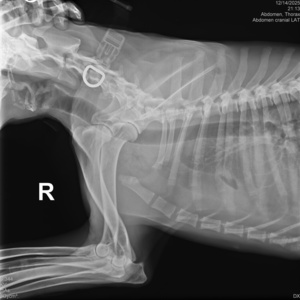

گالری تصاویر

رادیولوژی و سونوگرافی حیوانات در تهران